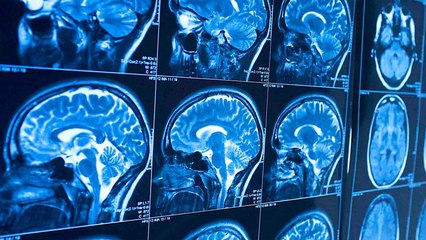

Cerveau : voici la technique à adopter pour gérer facilement un conflit